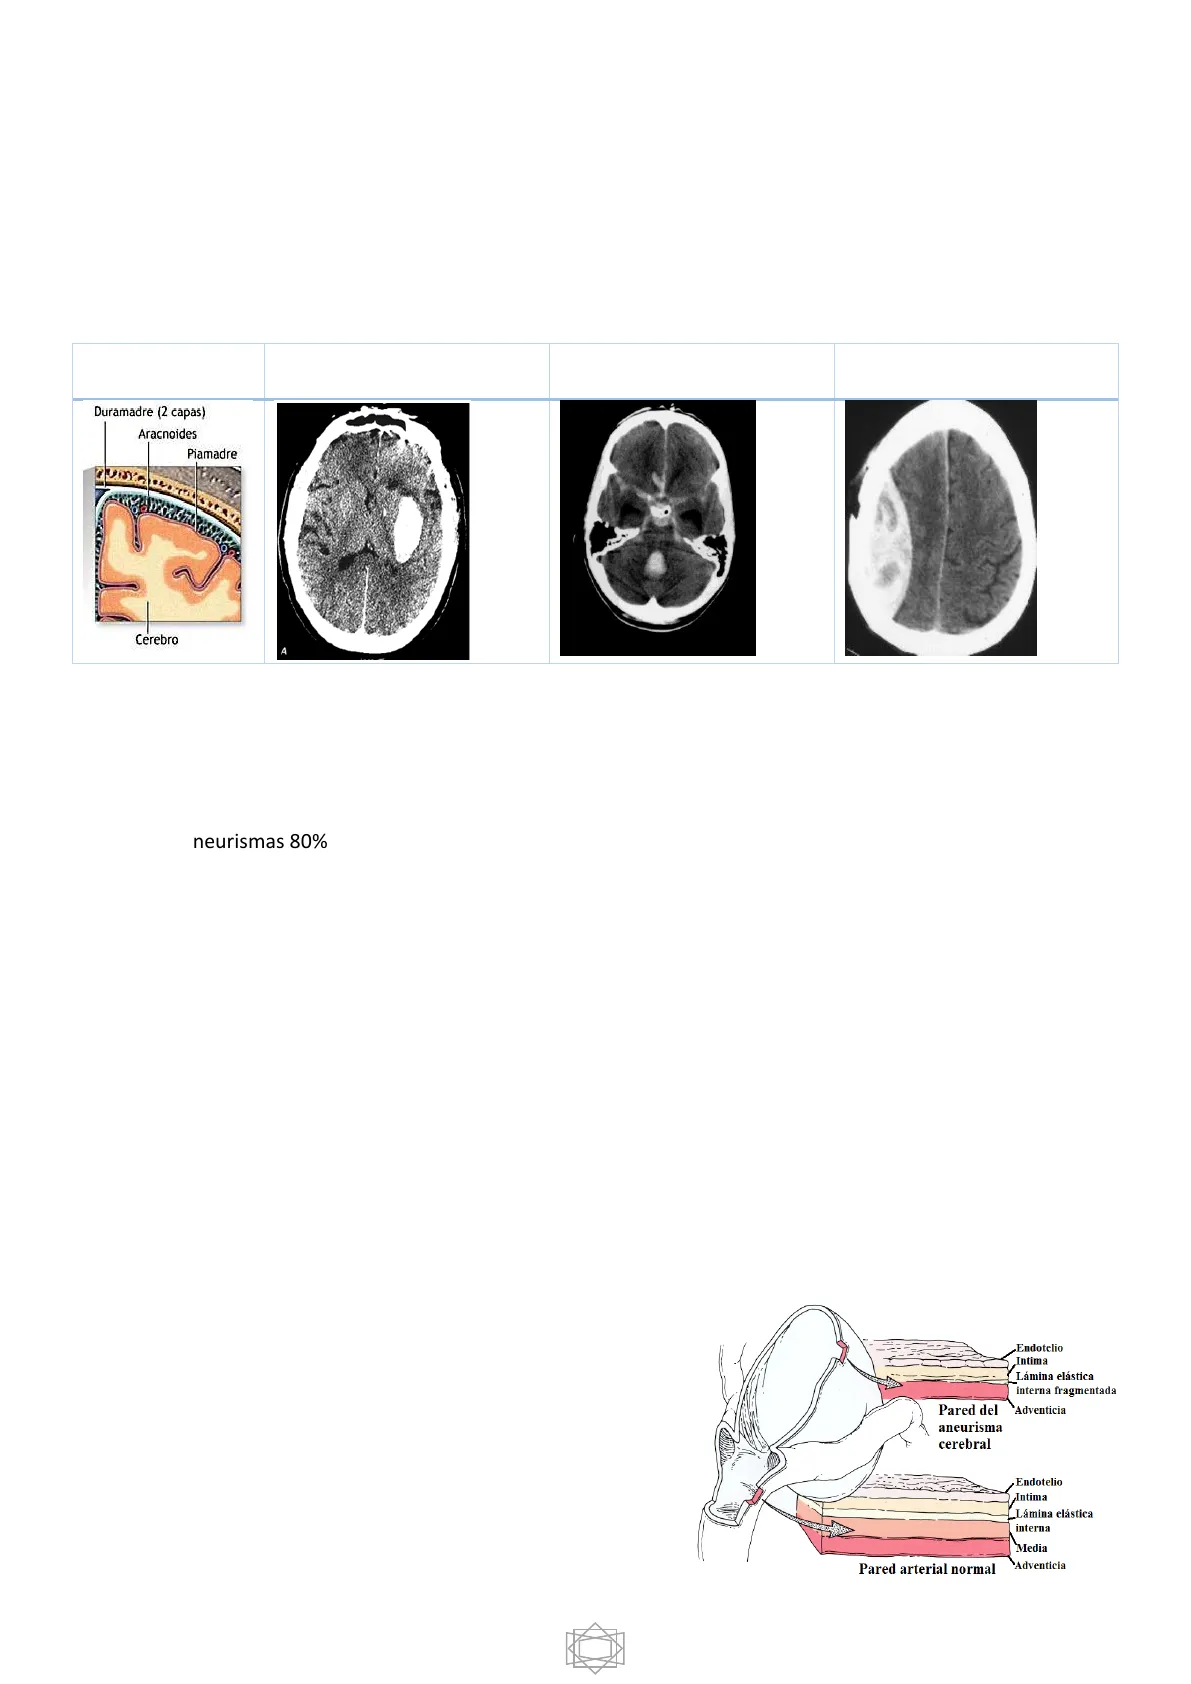

Hemorragia intraparenquimatosa Duramadre (2 capas) Aracnoides Piamadre Cerebro A Hemorragia subaracnoidea Hemorragia subdural/epidural

La pared arterial normal está formada por endotelio, íntima, lamina elástica interna y externa y una media. En los aneurismas medial GAP, lo que pasa es que no tenemos media. Este medial GAP siempre va a aparecer en las bifurcaciones arteriales.

Endotelio Intima Lámina elástica interna fragmentada Adventicia Pared del aneurisma cerebral Endotelio Intima Lámina elástica interna Media Pared arterial normal Adventicia 1FC VI Neurocirugía María García Pérez, Lorena Luque García, Ana Montiel Rey